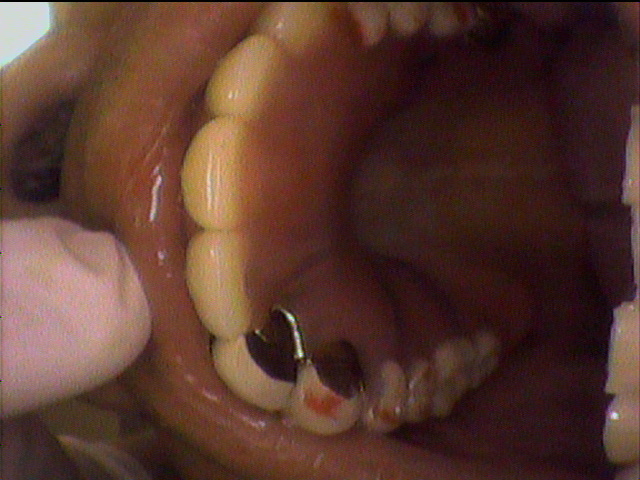

本日、出来上がりました自費の部分入れ歯ー下顎メタルプレートの症例です。

81歳の女性OUさんはとけも若々しいかたで、上下ともに、ぶぶん入れ歯ですが、今回は下顎の左右の奥歯のメタルプレートの入れ歯を新しく作りました。

自費によるメタルプレート義歯で、薄く丈夫な義歯として、とても舌感の良好な状態にすることができ、さらに自由な義歯の設計ができるため、残っているはにかける針金は白金加金で作成し、残存歯にやさしい設計となっており、舌に触れるバー部分はコバルトクロム合金で、丈夫に薄く作ってあります。

(参考代金;30万円)